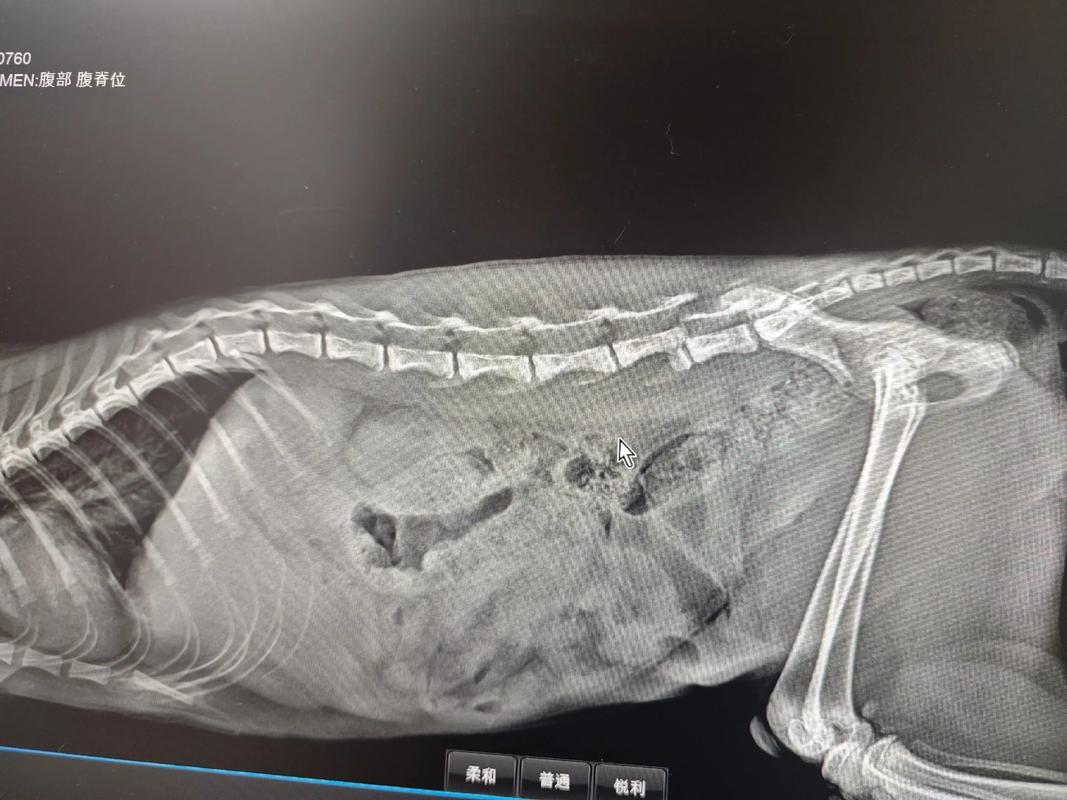

猫咪摔断脊椎

〖壹〗、猫咪的脊椎一般不容易断裂,如果猫咪摔伤了,可能会出现脊椎骨折或错位的情况,宠主需要及时把猫咪带去宠物医院检查,如果猫咪的运动神经没有明显的损伤,就可以尽快通过手术复位,术后积极做复建,也可以让猫咪恢复到正常状态。

〖叁〗、猫脊椎断了会出现以下症状:下肢瘫痪:由于脊椎是支撑身体运动的重要结构,一旦断裂,很可能会影响到猫咪的下肢运动功能,导致瘫痪。大小便失禁:脊椎断裂还可能损伤到控制大小便的神经,使得猫咪无法自主控制排泄。触摸脊柱部位无反应:断裂的脊椎部位在触摸时,猫咪可能不会有明显的反应或表现出疼痛。